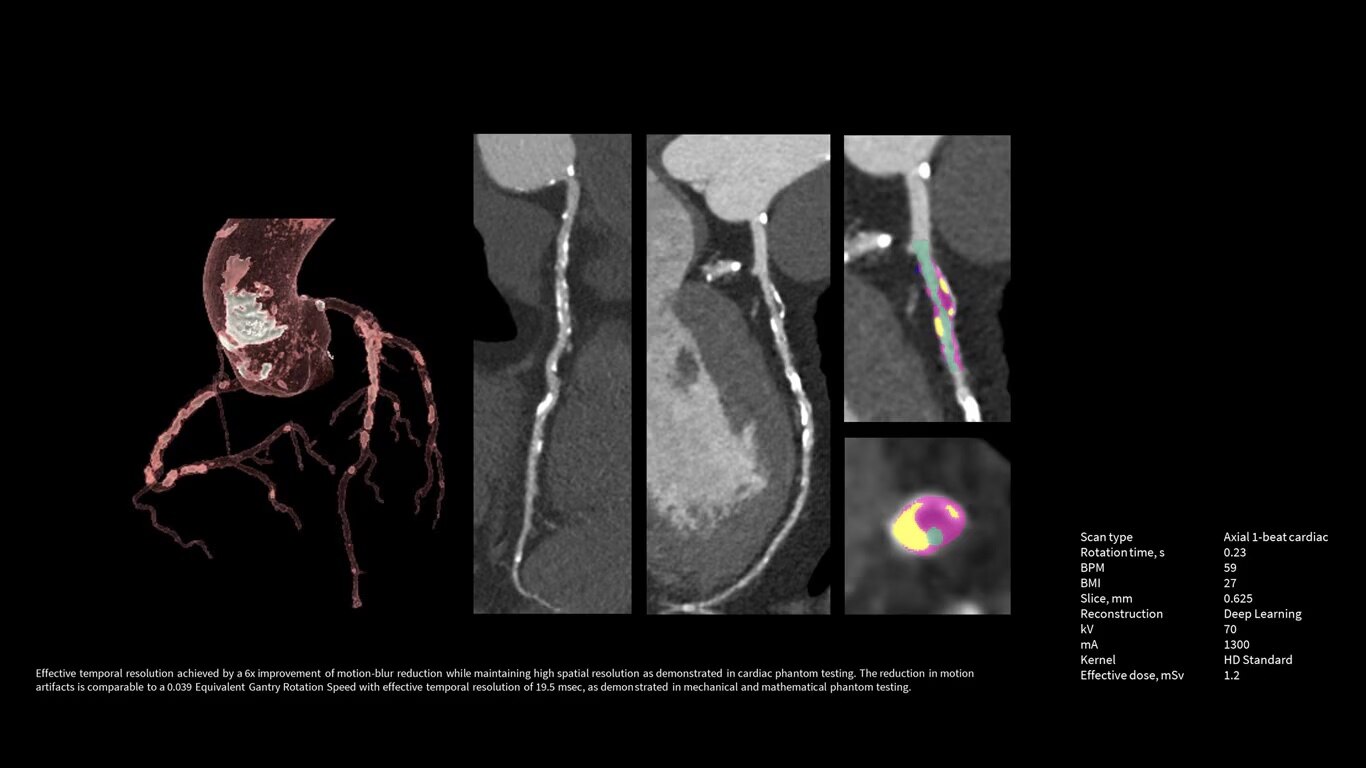

Upgrade to the industry's fastest rotation time

The Revolution Apex platform allows you to upgrade your gantry rotation speed. You can start with 0.28 sec gantry rotation time, and at any point in time when you need to advance your cardiac capability, you can upgrade to 0.23 seconds per rotation with the industry’s fastest rotation time.